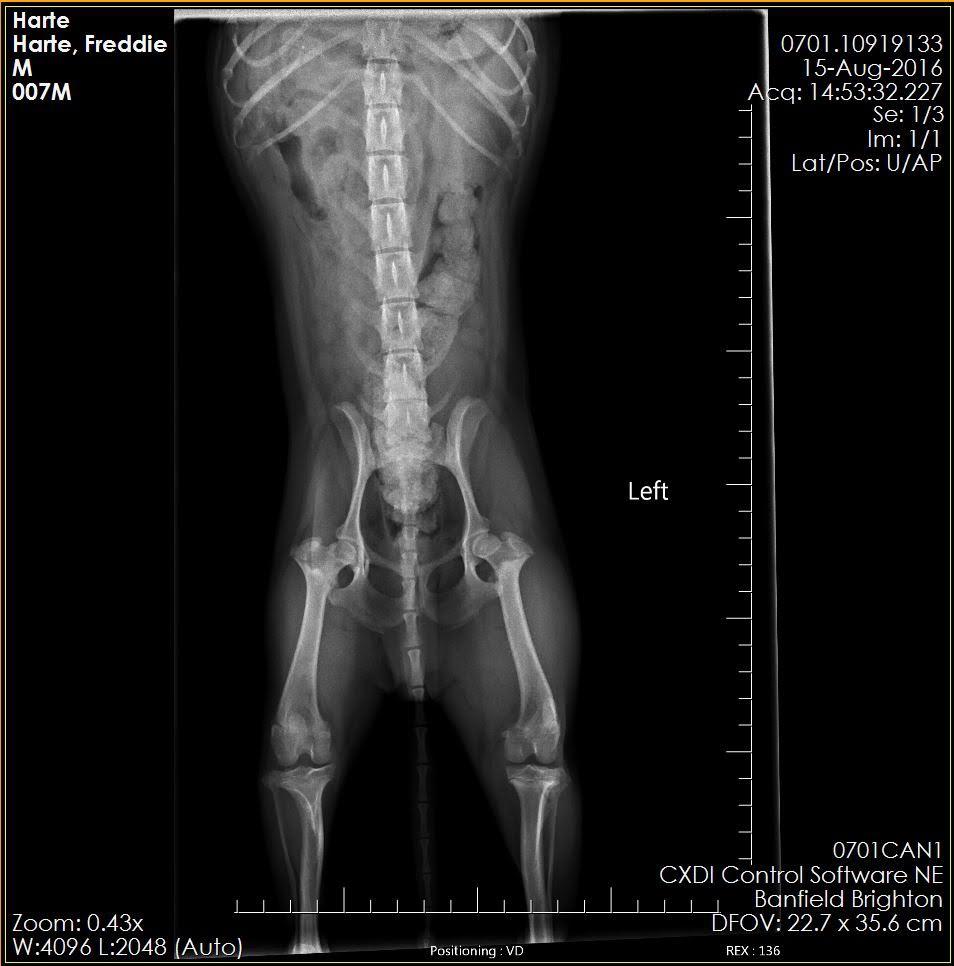

these are X-rays of my 1.5-year-old Yorkie Shih Tzu Mix or a Shorkie-Zu, his name is Freddie. He sometimes limps but mostly he doesn’t. He has as you can see muscle built up on his left leg. It seems like he limps on both of them when he does but he doesn't do it consistently. He had a cryptic orchid that has been removed. I have been told they don't know what is wrong with him.

I'm sorry to hear about Freddie Harte's limping. I am not seeing any obvious defects on this x-ray. The challenge is that the findings on exam are extremely important in trying to diagnose orthopedic issues; it would help to know if Freddie has proprioceptive deficits in his hind end, decreased range of motion, muscle atrophy, medial buttressing, etc as well as trying to localize any pain that may be contributing to his limping - all of this information would be combined with findings on x-ray to try to reach a diagnosis. Small dogs such as Shih Tzus are prone to luxating patellas, which may not always be evident on an x-ray but would be detected on exam. Did your vet discuss the option of referral to a specialist for a more concrete answer? I'm happy to give you my input on the x-ray - but referral to an orthopedic specialist who will be able to put their hands on your dog, as well as look at these x-rays, will give you much more beneficial input. I know its frustrating to have a chronically limping dog without an answer! I hope this helps!